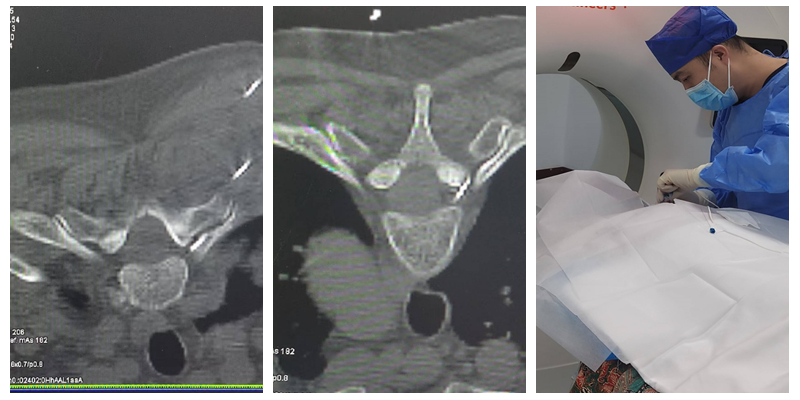

能完成该标准要求的绝大多数手术,包括选择性神经根阻滞技术、交感神经丛(干)介入医治技术、颅神经介入医治技术、神经射频调制技术、腰椎间盘介入医治技术、颈椎间盘介入医治技术、外周神经射频技术、脊髓电刺激、椎体成形术、硬膜外造影术、椎间盘造影术等。

腰椎间盘介入医治手术